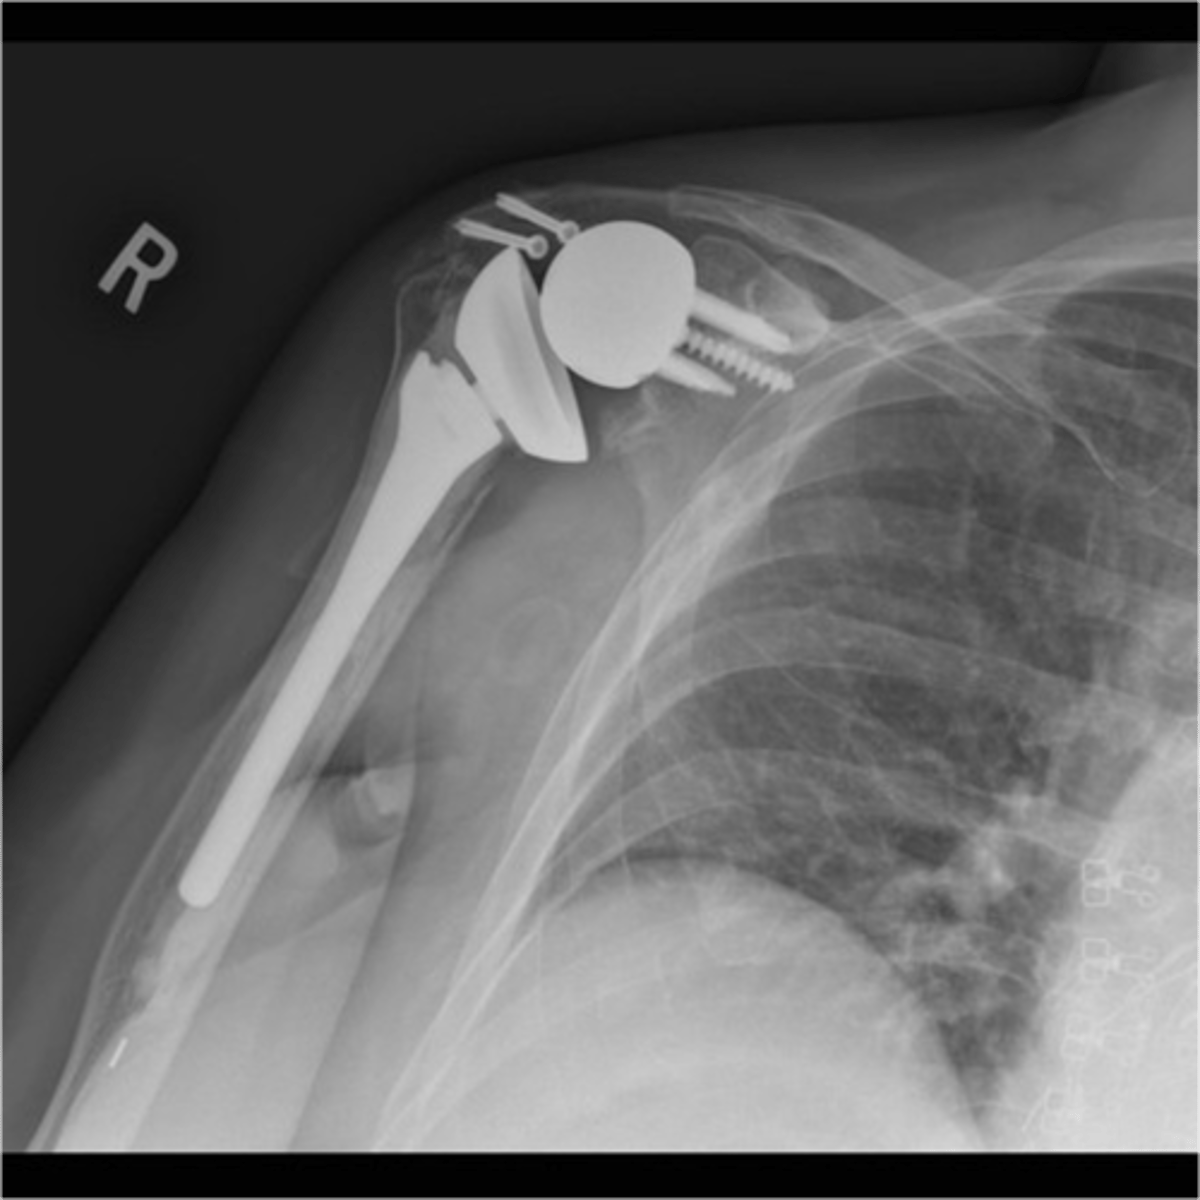

RTSA

What is this image depicting?